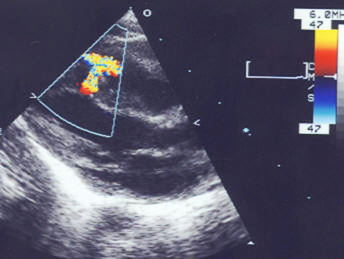

- echocardiography